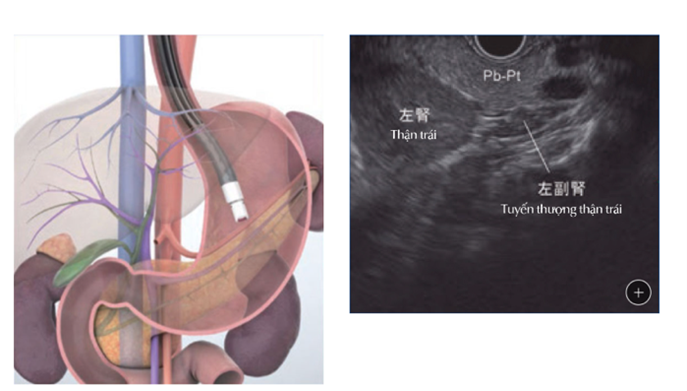

Nội soi đường tiêu hoá trên có thể được thực hiện như một phần của siêu âm nội soi để xem xét thành của đường tiêu hóa, cũng như các hạch bạch huyết lân cận và các cấu trúc khác ngay bên ngoài đường tiêu hóa. Ví dụ, nếu có một khối u trong thành thực quản hoặc dạ dày, siêu âm có thể cho biết nó đã phát triển đến (hoặc xuyên qua) thành bao xa và liệu nó có thể đã đến các hạch bạch huyết gần đó hay chưa. Từ ruột non, siêu âm nội soi cũng có thể được sử dụng để xem tuyến tụy, túi mật hoặc đường mật.

Nội soi siêu âm qua dạ dày

Đối với thủ thuật này, một ống nội soi được gắn một đầu dò siêu âm nhỏ ở đầu ống. Ống được đưa vào đường tiêu hóa và có thể được đưa theo các hướng khác nhau để nhìn vào thành ống tiêu hóa các hạch bạch huyết lân cận và các cấu trúc khác. Đầu siêu âm phát ra sóng âm thanh và thu nhận tiếng vang khi chúng dội lại từ các cấu trúc này, và tiếng vang được chuyển thành hình ảnh trên màn hình máy tính. Nếu thấy các khu vực nghi ngờ như hạch bạch huyết to hơn bình thường, có thể đưa một cây kim rỗng qua ống nội soi vào những khu vực này để lấy mẫu sinh thiết.